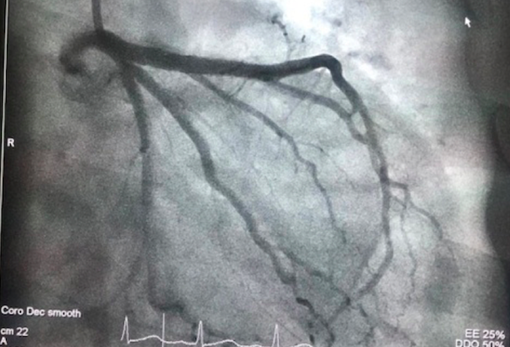

Cụ ông L.H.L. sinh năm 1927, ngất đột ngột sau khi uống rượu vào ngày mùng 3 Tết. Sau khi được sơ cứu tại bệnh viện gần nhà, cụ L., được chẩn đoán là nhồi máu cơ tim cấp thành dưới có biến chứng loạn nhịp tim gây ngất, và chuyển cấp cứu đến Bệnh viện Đại học Y Dược TP Hồ Chí Minh (BV ĐHYD).